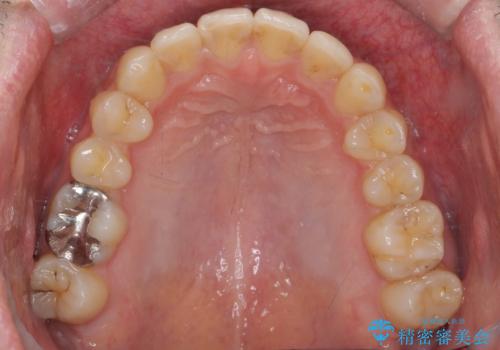

出っ歯と歯のねじれ 非抜歯で 30代男性

- 前歯の並びを気にして来院。

右の歯並びが1本分上が前にずれていました。

本来は抜歯して上の前歯を引っ込めるか、歯を一本分上の奥歯を後ろに下げるやり方が正攻法ですが、

ご本人はそこまでご希望されていませんでした。

奥歯のかみ合わせを特に変えず、前歯の並びを整える治療をおこないました。

奥歯のかみ合わせは1本分ずれているとはいえ、1歯対2歯の交互のかみ合わせになっているため、そのままにしてもそこまで大きなデメリットはありません。

右上のかみ合わせをそのままにするため、上下の正中は合わない仕上がりとなります。